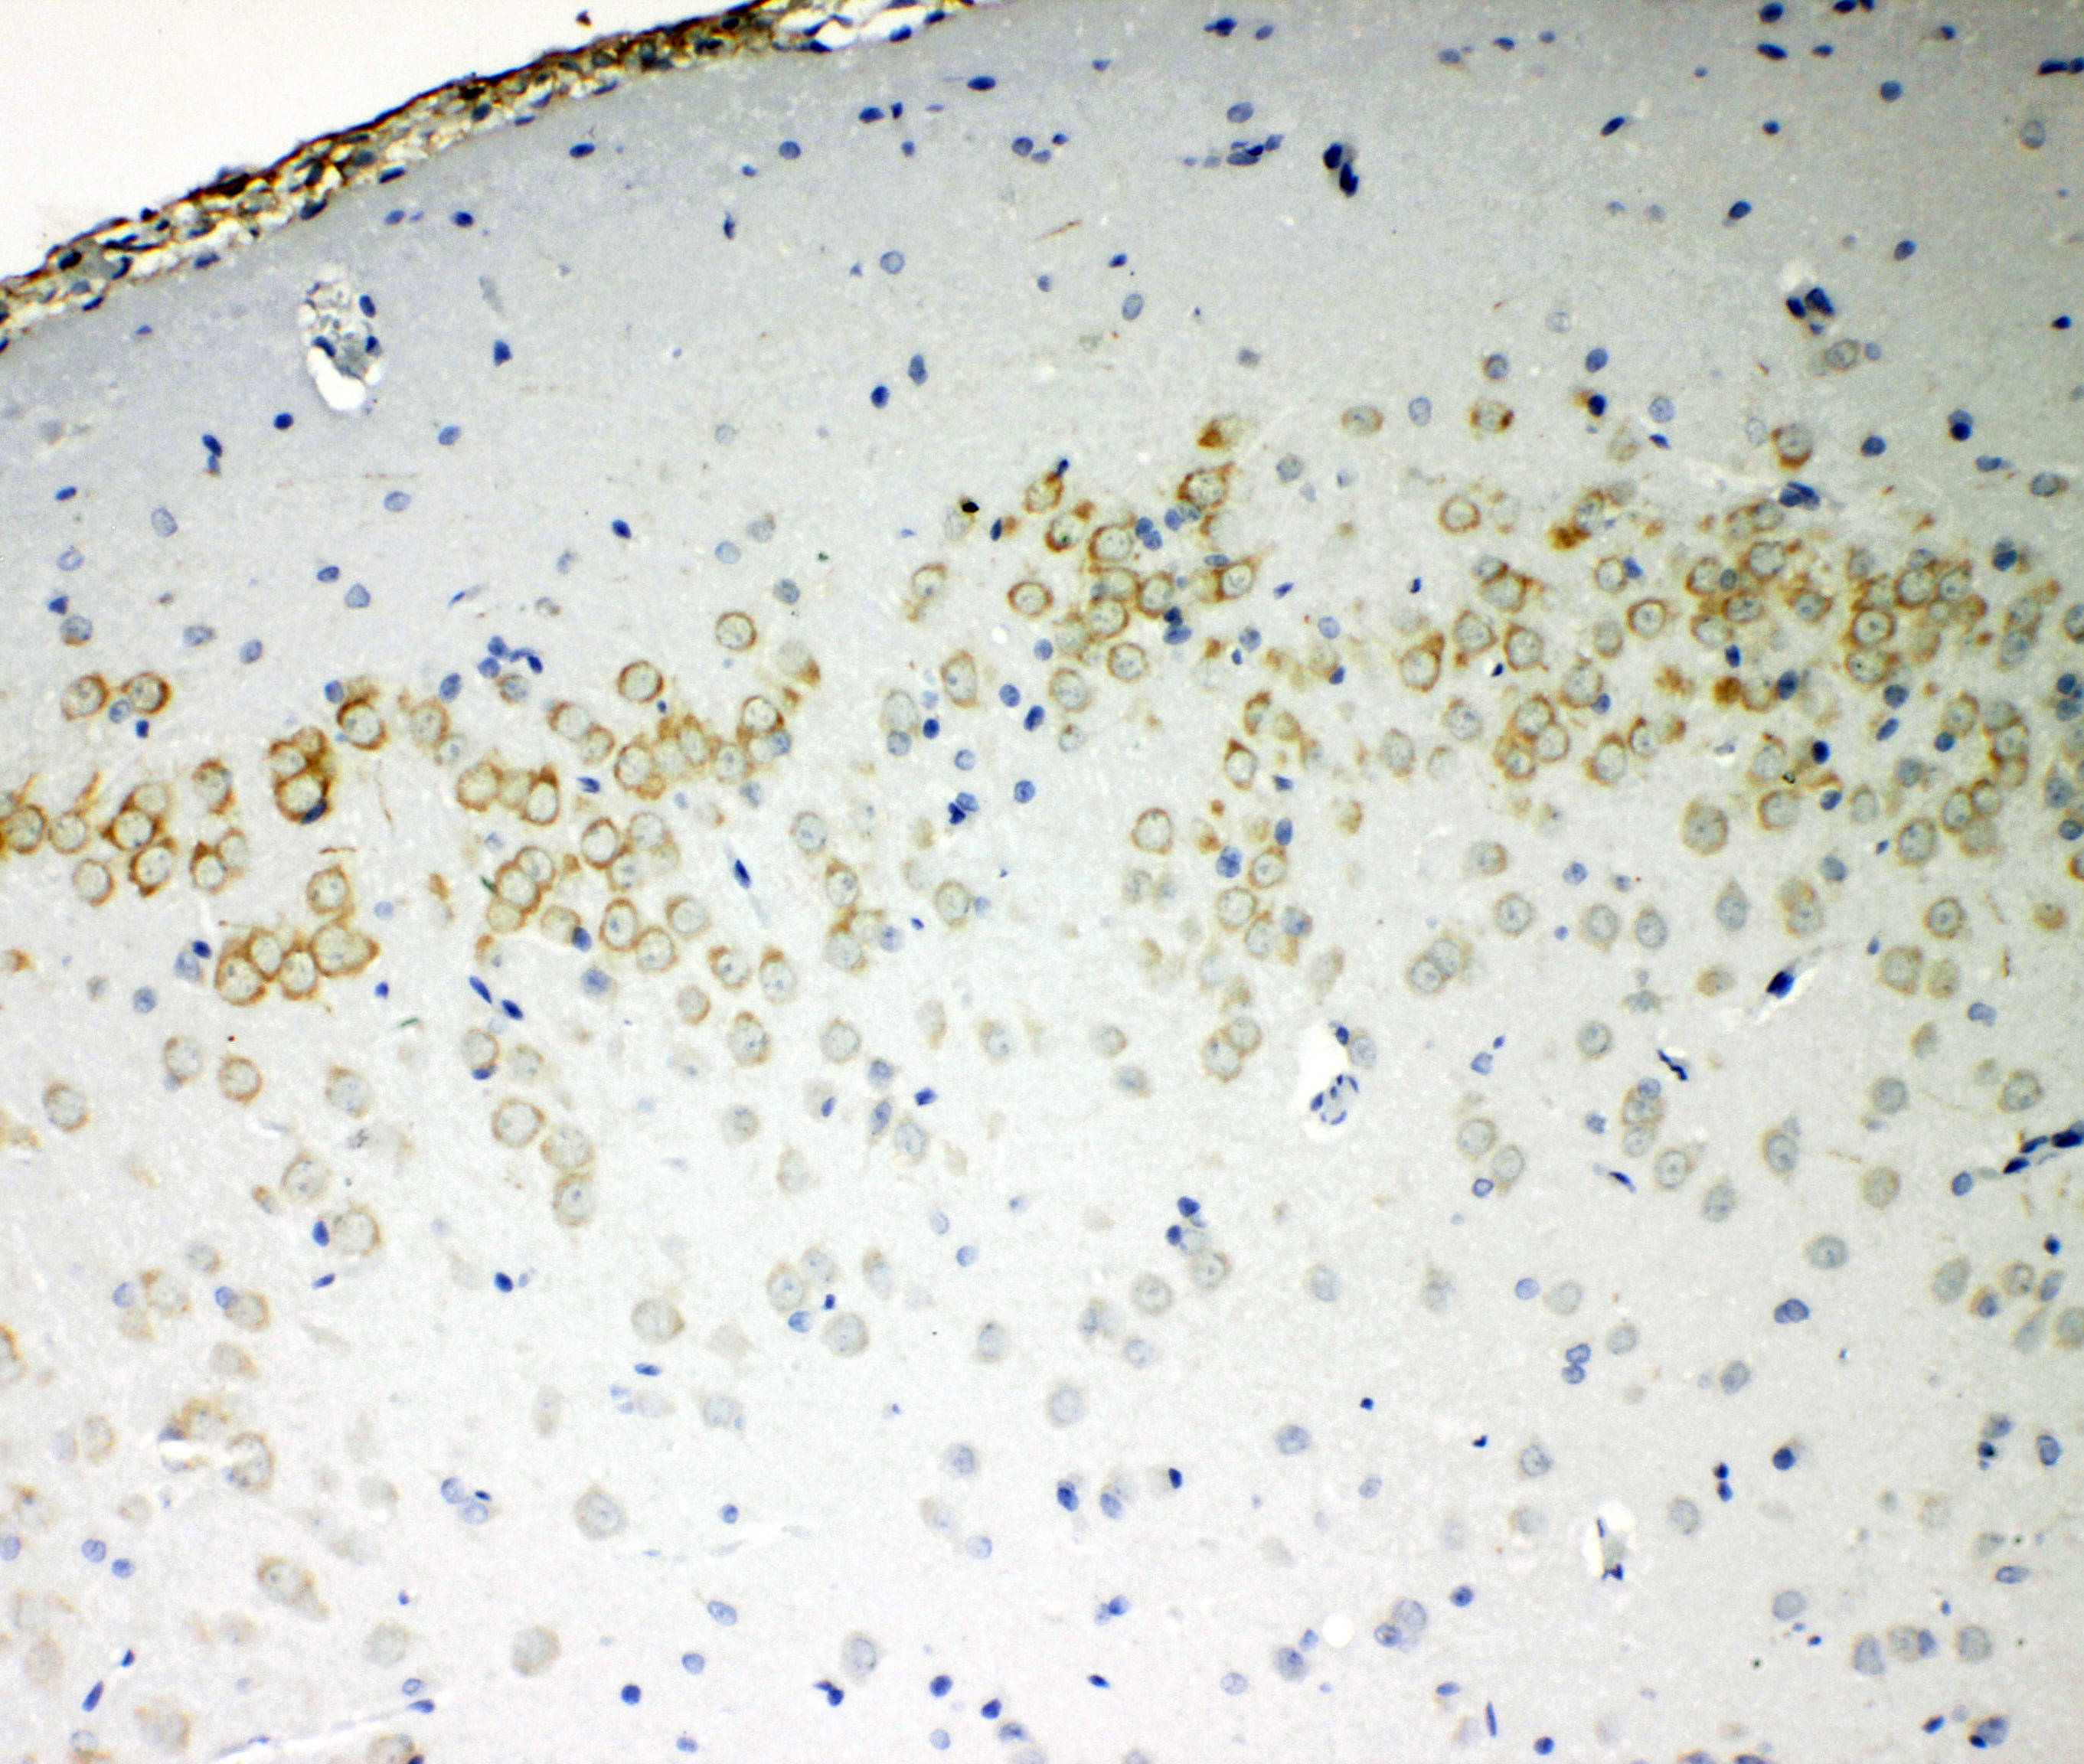

IHC analysis of VE-Cadherin/CDH5 using anti-VE-Cadherin/CDH5 antibody (BA3032).

VE-Cadherin/CDH5 was detected in a paraffin-embedded section of rat brain tissue. Biotinylated goat anti-rabbit IgG was used as secondary antibody. The tissue section was incubated with rabbit anti-VE-Cadherin/CDH5 Antibody (BA3032) at a dilution of 1:200 and developed using Strepavidin-Biotin-Complex (SABC) (Catalog # SA1022) with DAB (Catalog # AR1027) as the chromogen.